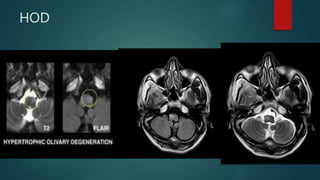

HOD